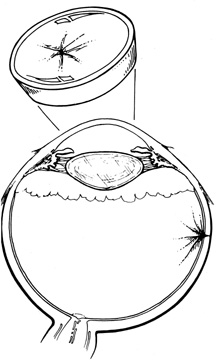

After placement of diathermy, the silicone implant is trimmed to fit beneath the scleral flaps, and nonabsorbable 4-0 mattress sutures are placed in the scleral flaps. The flaps then are closed with temporary suture ties. An encircling band may be placed through the groove of the implant, beneath the scleral flaps and around the globe.

The band is anchored with scleral tunnels or mattress sutures. The ends of the band are joined with a tantalum clip, nonabsorbable suture, or silicone sleeve (Fig. 27). Drainage of subretinal fluid usually is required and is described later.

Fig. 27. Placement of implant in scleral dissection and closure of scleral flaps.